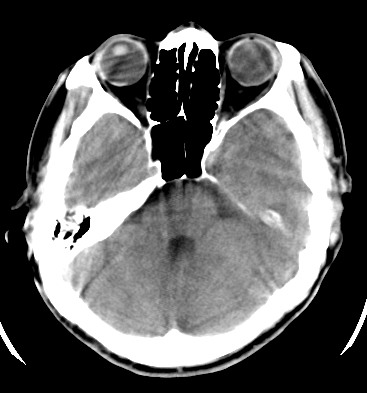

标题: CT17787:头ct,请帮忙看看右顶部有无异常 [打印本页]

标题: CT17787:头ct,请帮忙看看右顶部有无异常

男,58岁,偶有头疼

未见明显异常。右顶部低密度影为深入的脑沟。

增宽的脑沟!无异常!

是宽大的脑沟,局部不象有萎缩现象

增宽的脑沟

诊断依据:

低密度影周围脑组织边缘均有一层脑灰质覆盖。

正常啊,是对右顶增宽脑沟有疑问吗